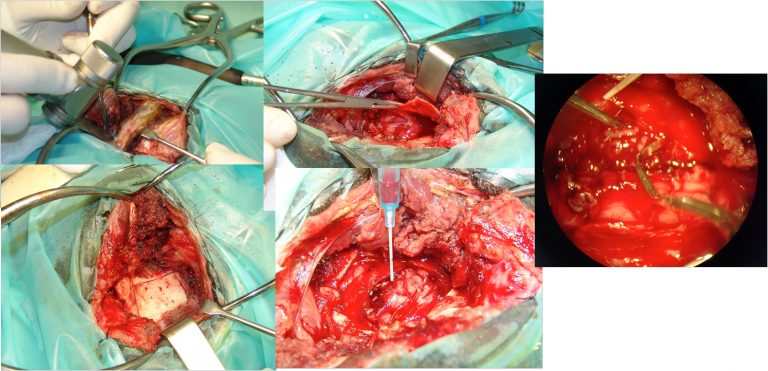

Traitement chirurgical

- Résection des deux tables du calvarium, ouverture du sinus frontal

- Dissection sous microscope

- Mise en place d’une prothèse de PMMA

- Plus large que de défect osseux pour éviter toute pénétration